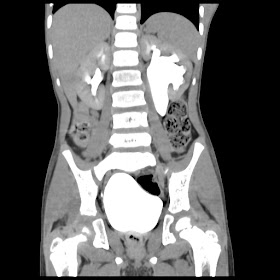

A 07 years old child with left side of abdomen pain

current CT images: